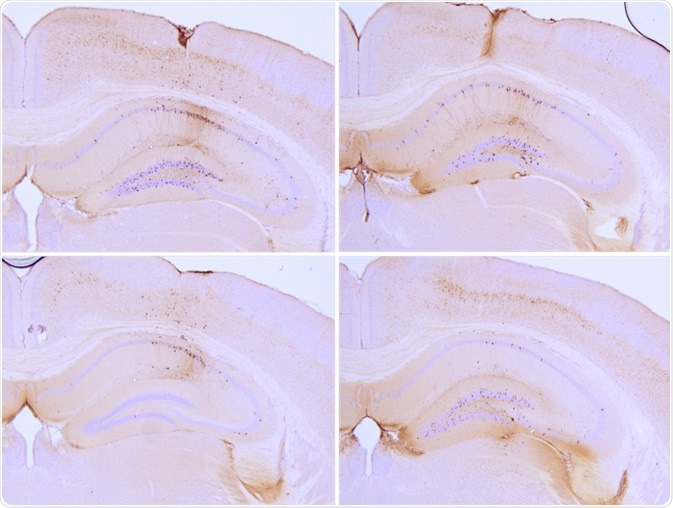

Particular tau PFFs have been injected into P301L mice, where they seed tau aggregation and induce tau pathology in the hippocampus. Fibrils and monomers are available both in the full-length isoform of the tau protein (2N4R or Tau-441) or a truncated form (K18). K18 tau has a molecular weight of approximately 15 kDa, whereas Tau-441 has a molecular weight of around 46 kDa.

Immunohistochemistry analysis of P301L mouse hippocampus injected with K18 P301L tau PFFs (SPR-330) shows seeding of tau pathology at injection site. AT8 (pSer202/pThr205) tau antibody shows tangle-like inclusions. Experiments performed at reMYND N.V. Image Credit: StressMarq Biosciences